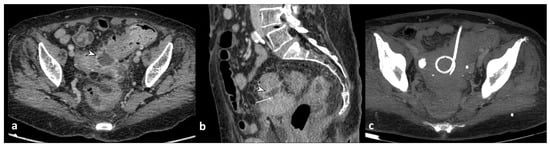

Figure 9. Axial contrast-enhanced CT images (a,b) show the presence of pericolic air bubbles and air collections (arrows) and diffuse peritoneal free fluid (asterisks); lung window axial CT (c) shows distant free air (arrowheads) below the abdominal wall.